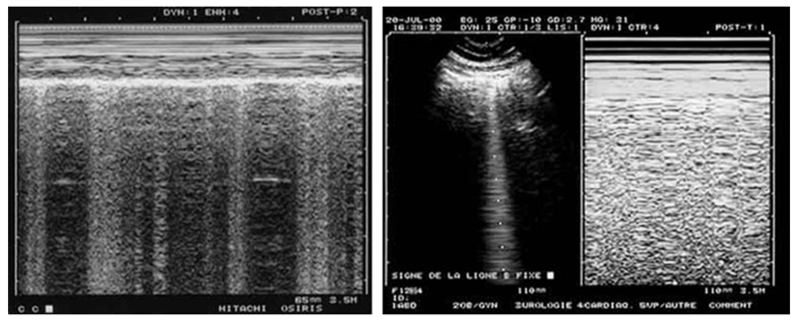

Fig. 1 This figure is devoted to show that static images can indicate dynamic phenomena. To the left, the alternation of vertical hyperechoic lines shows that B-lines come and go through the shooting line of the M-mode: lung sliding is present. Note also the marked dyspnea in the Keye’s space: patient likely not intubated. To the right, the M-mode shows a homogeneous field below the Keye’s space, indicating that the B-line taken by the shooting line is standstill.